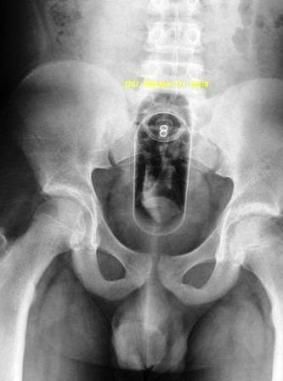

The teen stated in his father’s presence that he had been showering and then slipped on something and fell. He reported that something had gone into his rectum when he fell. He thought it was a toothpaste dispenser. His story changed a few seconds later. This time he said that when he got out of the shower he inadvertently sat on a toothpaste dispenser that was on the toilet seat. The teen gave yet another account to the radiologist when x-rays films (Figure-click to enlarge) were being obtained and when his father was not present. That version of the story was equally unbelievable.

The teen was taken to the operating room and a toothpaste dispenser was recovered from his rectum. After interviewing the parents, the mother’s boyfriend, and the teen, there were no red flags in their interviews. The story as relayed by the mother and boyfriend fit the timeline in the teen’s disclosure. The teen’s final statement was that this had been an attempt at self-stimulation. The case was closed as non-abuse. The teen was discharged to his mother’s home for convalescence.